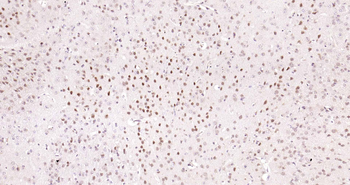

IF, IHC-Fr, IHC-P, WB

应用稀释比例:WB=1:500-2000, IHC-P=1:100-500, IHC-F=1:100-500, IF=1:100-500